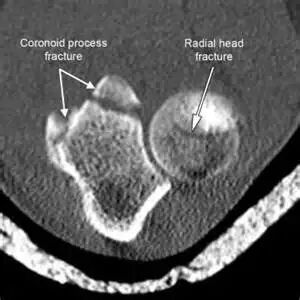

CT&MRI

偶尔我们需要利用CT或MRI